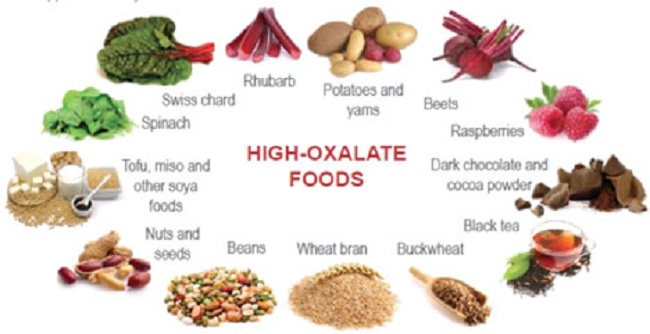

There is a truism in the sociology of occupational knowledge: “If all a doctor has is a hammer, then everything becomes a nail”. All modern medicine relies on overkill dosages of drugs or surgery as the standard of care (Jennifer Daniels, MD, The Lethal Dose, 2013). There are no drugs or surgery that can alleviate the symptoms of poisoning from a natural pesticide found in plant foods but also produced in the liver. With this professional void, treating oxalosis has mainly been left to nutritionists. So, if you ask a nutritionist about oxalates, you will get a predictable answer to reduce oxalates in your diet. This is insufficient because most oxalates are produced by poor metabolism in the liver. Oxalate is a natural pesticide found in plant foods, but also is internally produced mainly from fungus and vitamin C (see How Oxalates Ruin Your Health). Oxalosis manifests as a syndrome of three main symptoms: oxalate crystals in tissues and kidney; histamine, mucous attack in nasal passages; and pseudo-gout mainly from acidity and eating cooked meat.

First, I learned that calcium is needed as a co-valent chemical binder to oxalate before meals to eliminate oxalate through the bowel or oxalic acid through with urine through the kidney. Secondly, I learned that plant foods like spinach, almonds, chocolate, and soy and were loaded with toxic levels of oxalates, a natural pesticide that protects plants from insects, worms, and herbivores. I also learned that high doses of synthetic Vitamin D (10,000 mg/day as a steroid) without Vitamin K2, could also lead to kidney stones and oxalosis. An iron deficiency may come into the picture as discussed below.